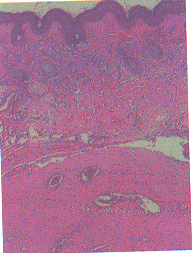

X线检查(包括颌骨、两手、右上肢、两侧锁骨及骨盆):上下齿槽骨骨质明显吸收;两手末节指骨除左无名指外,均呈膨胀性溶骨性破坏(图2);右尺骨近端背侧、左锁骨中段、右髋关节内下缘泪点旁及右股骨颈处均可见囊性破坏区。组织病理检查(头皮及左耳廓皮损):表皮基本正常。真皮中、深层有由细胞和基质构成的肿瘤,瘤体内血管较丰富(图3),细胞核圆形或椭圆形,有的为双核,胞浆丰富、淡染,有的呈空泡状,有的呈网状,有的胞浆中有嗜酸性细小颗粒,周围的间质呈均质嗜伊红性(图4)。两块标本病变一致。PAS染色阳性。

图3 幼年性透明蛋白纤维瘤病

皮损组织病理象

图4 幼年性透明蛋白纤维瘤病